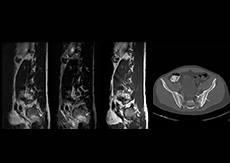

“In our lumbar spine MRI, the value of mDIXON TSE is so obvious. Normally we perform T1 and T2 scans in sagittal and transverse orientation.It used to take too much time to add a sagittal T2 with good fat suppression.But now, using mDIXON TSE, we get the sagittal T2 fat suppressed images ‘for free’, that is: without adding time.” “Diagnostically that is a great benefit. I sometimes see abnormalities in the fat suppressed sagittal T2 that would be quite challenging to notice in the T2 without fat suppression. There have been several diagnoses that I could make easier because of our exam setup with mDIXON TSE, such as sacrum insufficiency fractures and sacroileitis; these were more challenging with our previous exam setup.”